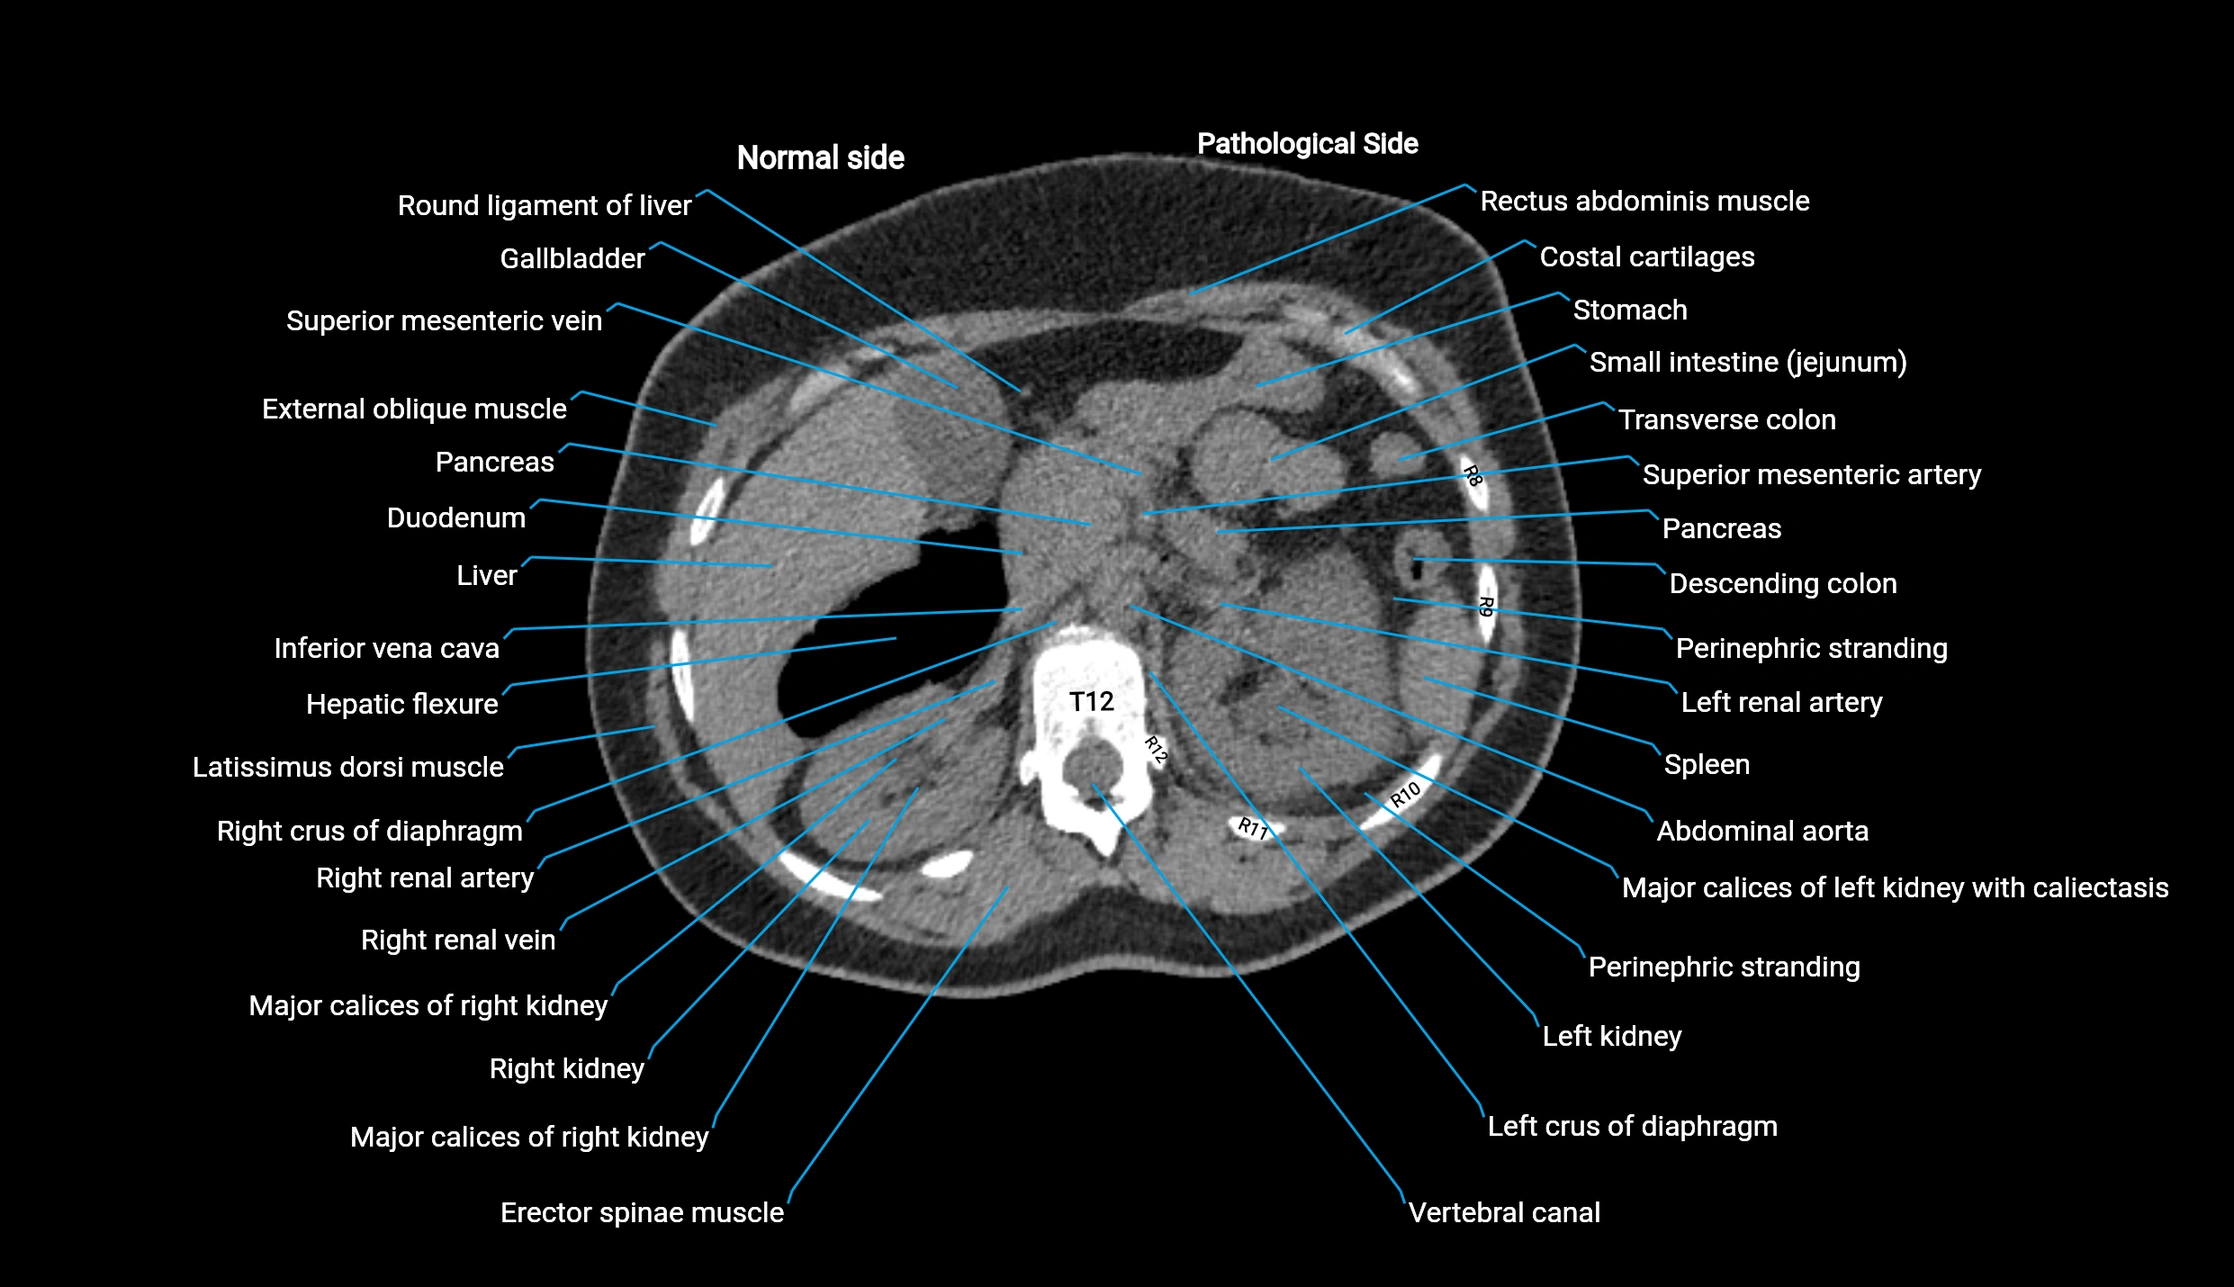

Post-Contrast CT (Contrast-Enhanced CT):

• Portal venous phase:

• Anterior right portal branch enhances intensely and homogeneously

• Clearly separates from posterior branch

• Branching pattern to segments V and VIII sharply defined

• Arterial phase:

• Slight enhancement but less conspicuous than in portal phase

• Coronal and sagittal reconstructions:

• Optimal visualization of segmental bifurcation

• Used for preoperative liver mapping

• CT liver segmentation:

• RAPV acts as the principal boundary landmark for dividing anterior vs. posterior right hepatic segments